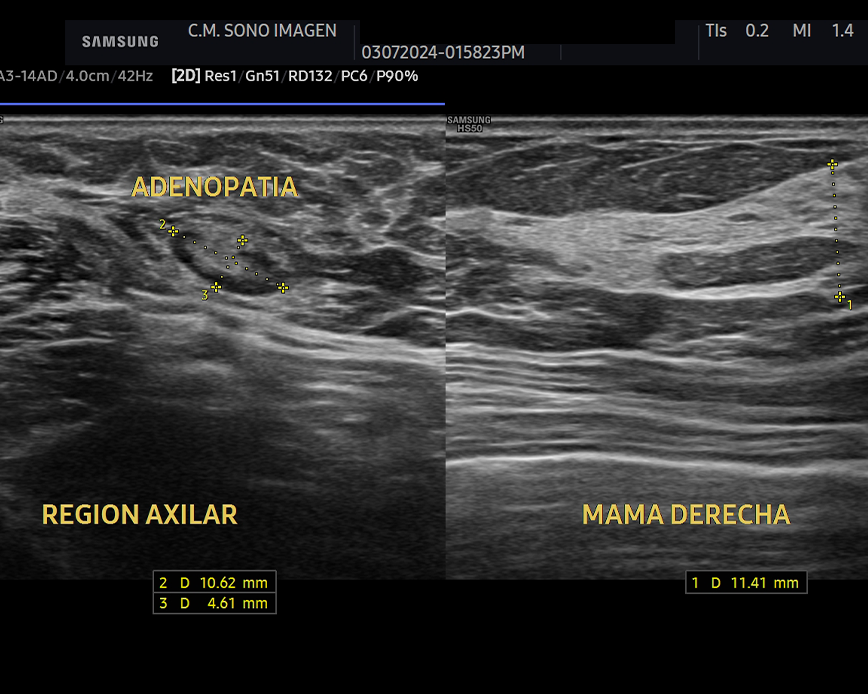

- glándulas mamarias

- ganglios linfáticos superficiales